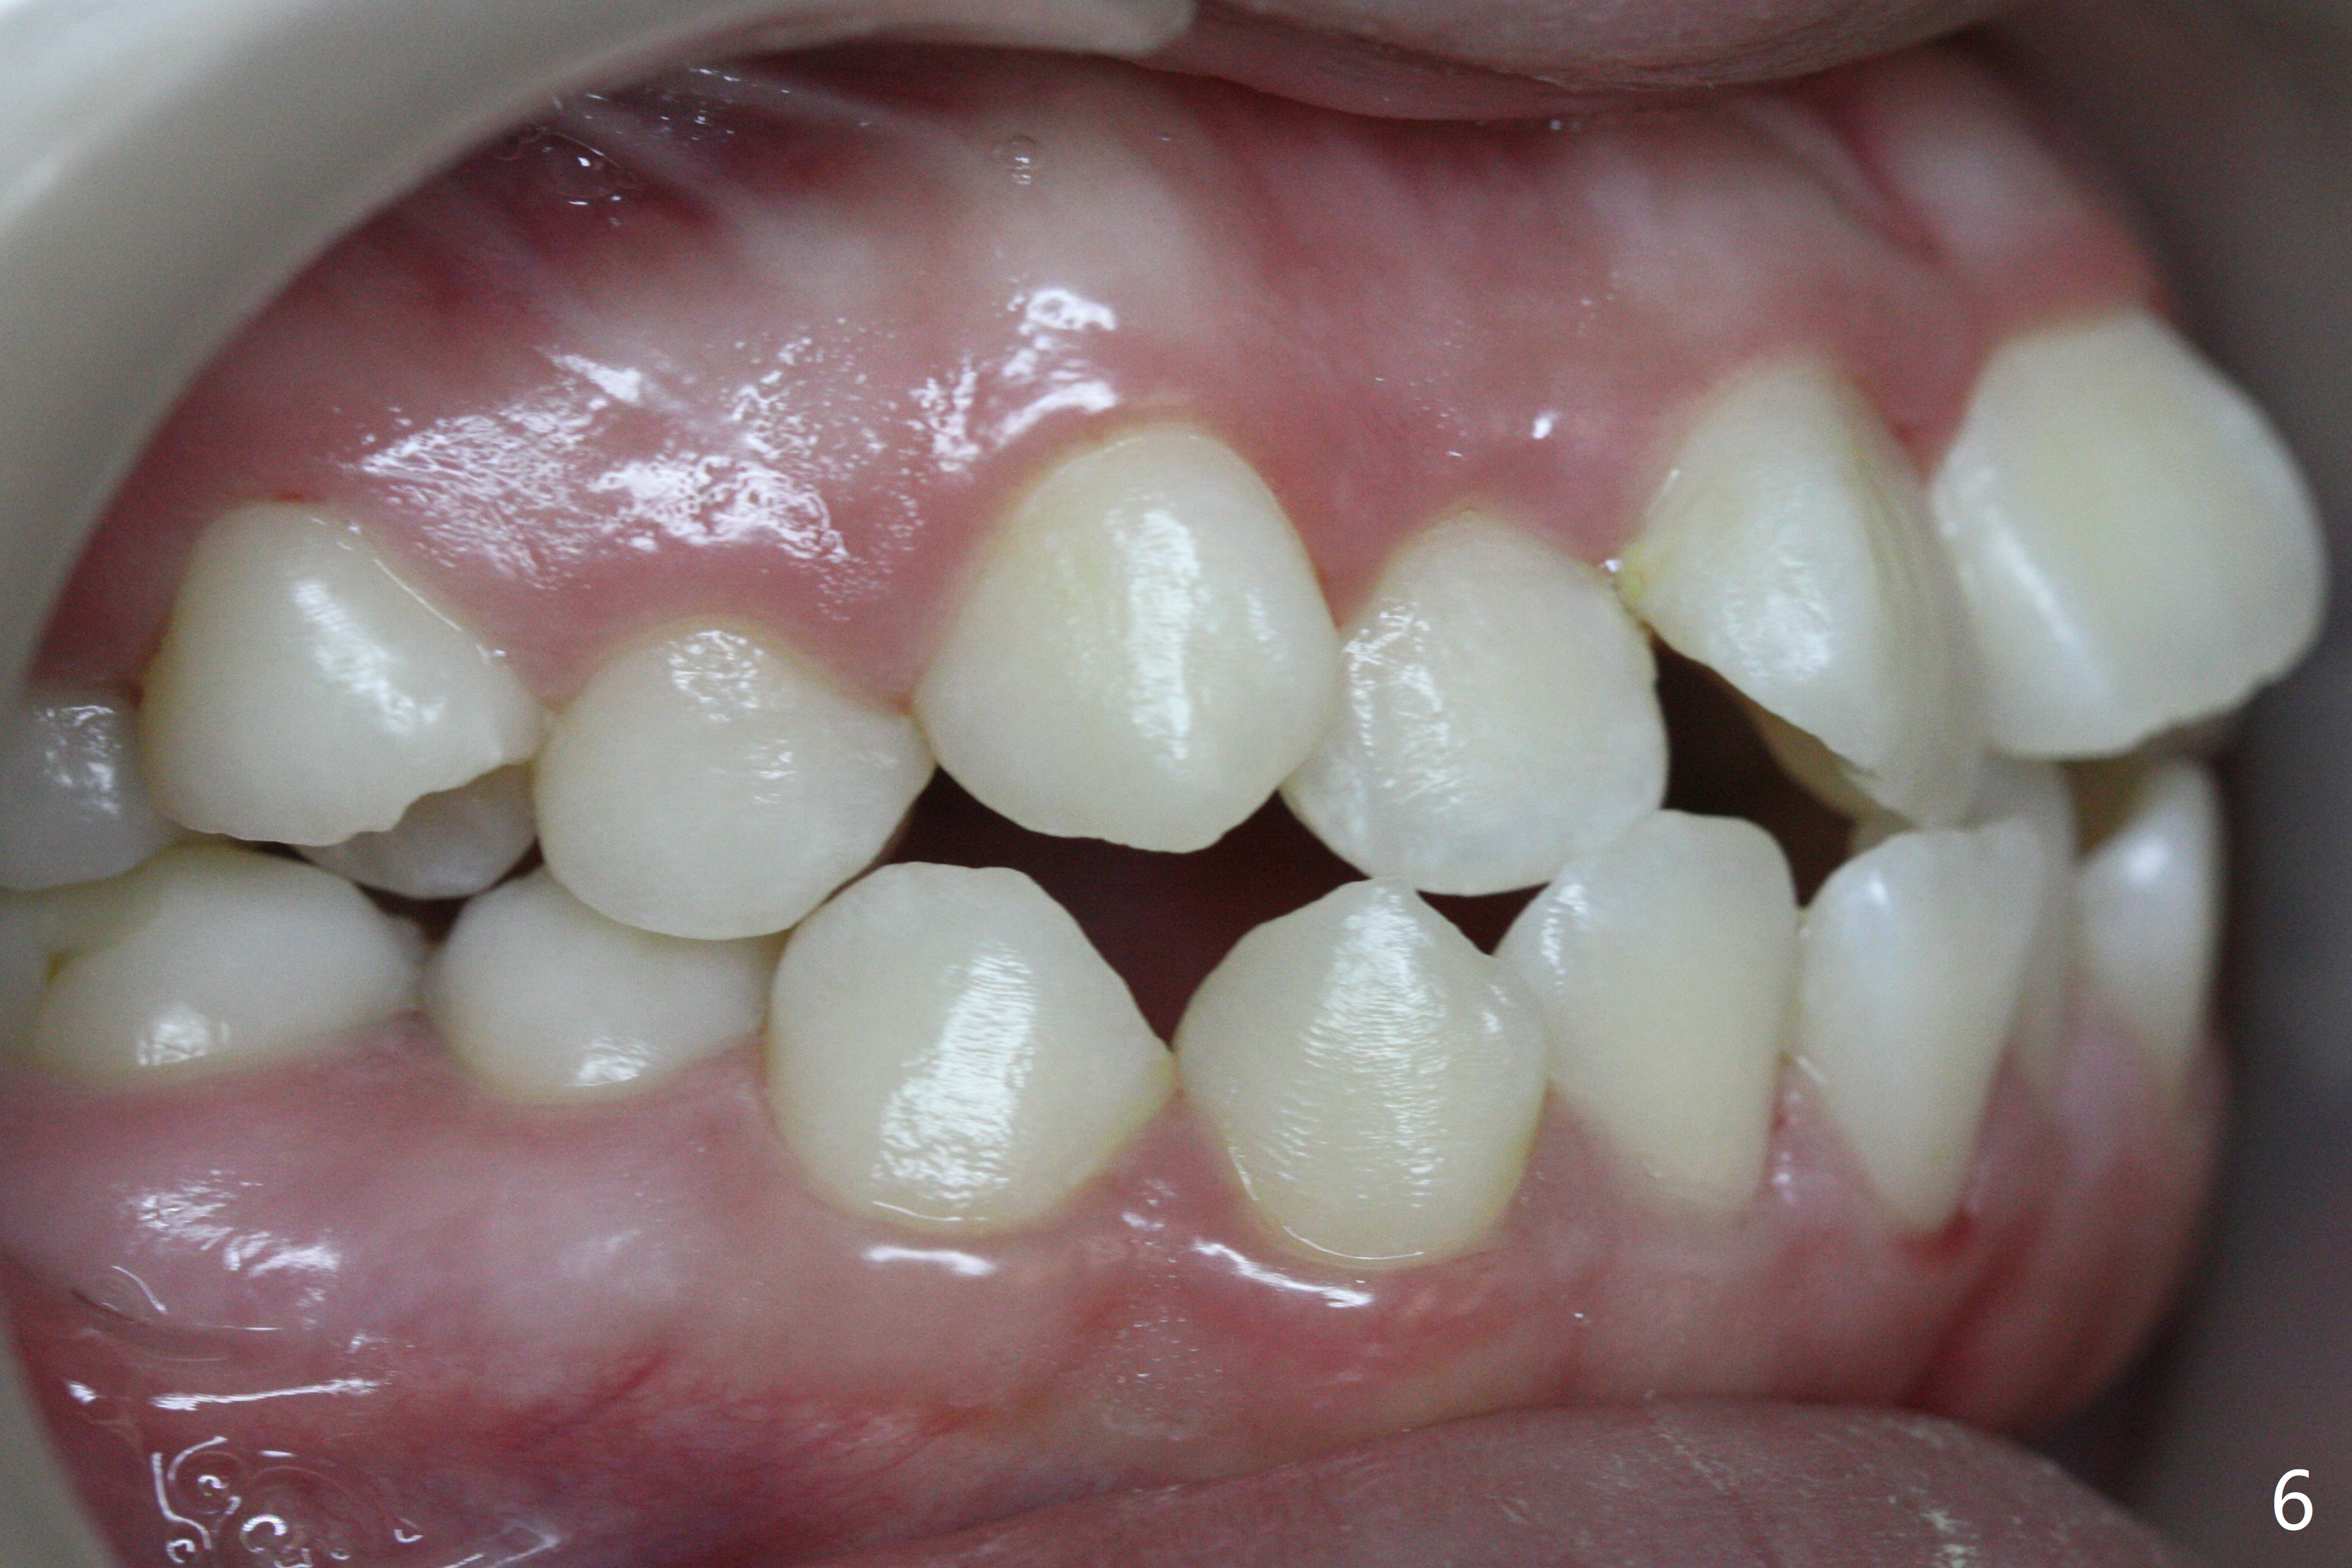

A 14-year-old woman has convex facial profile (Fig.1-4) with the upper midline shifted to the left (Fig.2). Since the roots of the 1st bicuspids are short (Fig.5), extraction should be easy. U3 will be retracted distal early with intention to correct the upper midline. With Class I occlusion at the canines and the 1st molars and good initial interdigitation (Fig.6-11), orthodontic treatment should be rewarding. Because of severe crowding (tight contact, Fig.12,13), place separators after extraction and place bands and brackets a few days later. Cephalometric analysis (Fig.14) shows that SNB is greater than SNA (82.4 vs. 81.8 degree); after extraction, retract the lower anterior teeth prior to the upper ones. It is easy to place separators after extraction (Fig.16,17).